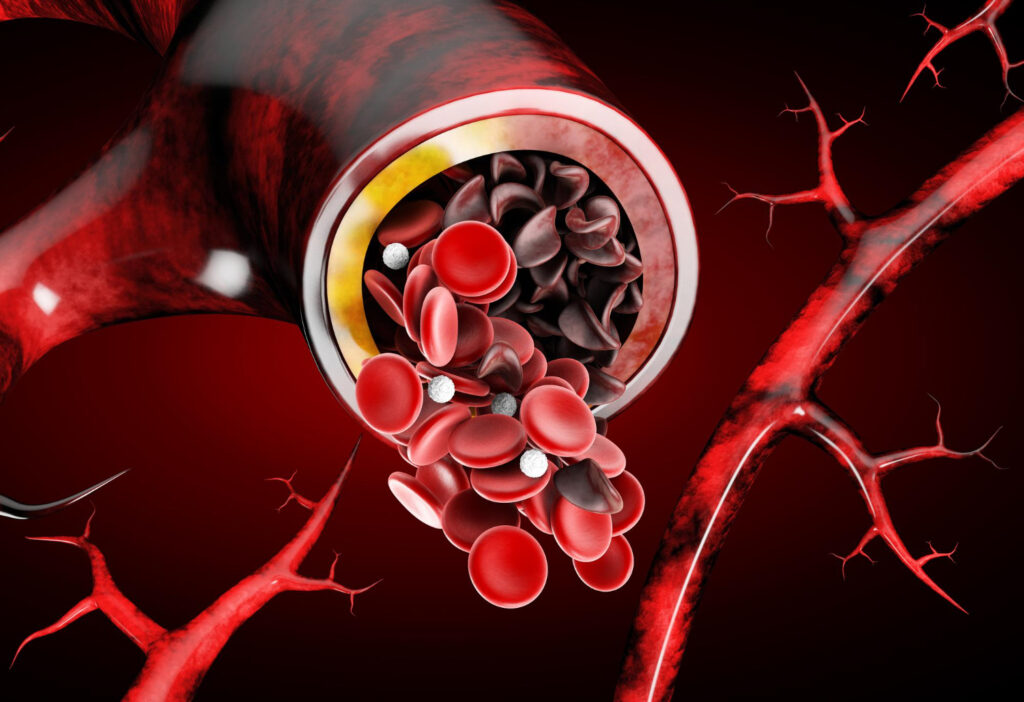

trombos / embolia

Trombos são coágulos de sangue que se formam dentro de um vaso e podem “tampar” parcial ou totalmente a passagem do sangue. Eles podem surgir por alterações na circulação, lesões na parede do vaso ou maior tendência do sangue a coagular, situações que podem acontecer, por exemplo, com imobilidade prolongada, cirurgias, varizes importantes, uso de alguns hormônios, tabagismo e certas doenças. Quando um pedaço desse coágulo se solta e viaja pela corrente sanguínea, chamamos de embolia.

Coágulos (trombos) se formam, em geral, quando acontece uma combinação de 3 fatores: sangue mais “parado”, lesão/irritação do vaso e maior tendência do sangue a coagular.